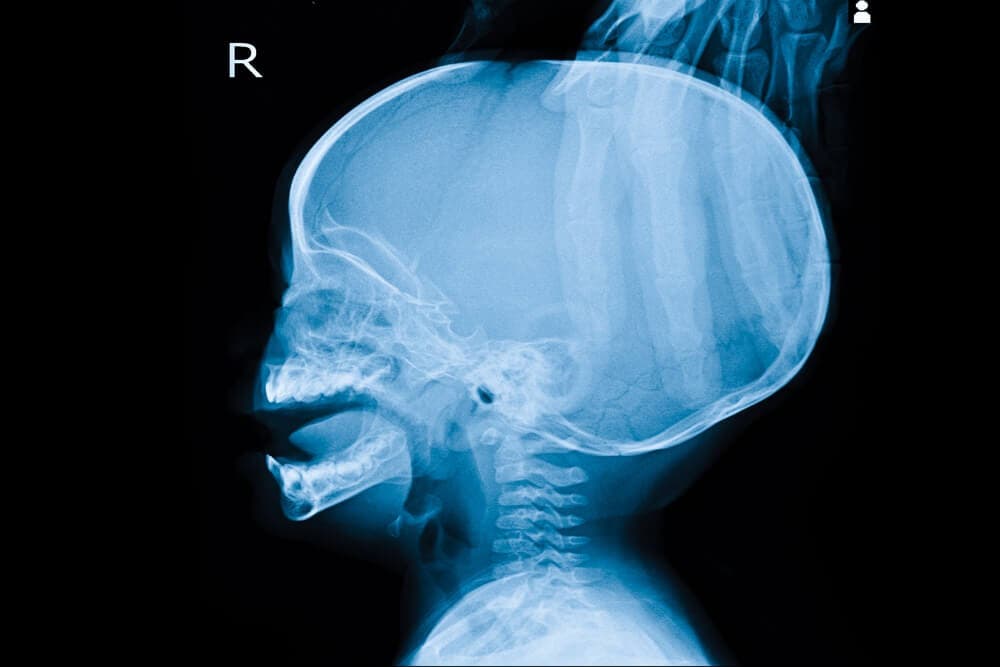

El organismo produce líquido cefalorraquídeo (LCR) continuamente. La hidrocefalia es un trastorno que se caracteriza por una acumulación anormal de líquido cefalorraquídeo (LCR) en el cerebro. Esa acumulación provoca un aumento excesivo de la presión en el cráneo.

- Pruebas de imagen, como una tomografía axial computarizada o una resonancia magnética, para detectar un aumento en el tamaño de los ventrículos.